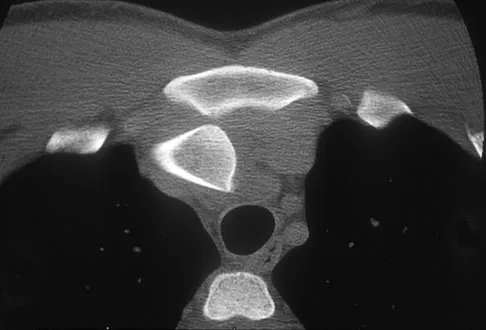

Question 55

The mother of a 3-month-old infant states that she has difficulty positioning the infant's legs during diaper changes. Examination reveals limited abduction of both hips and a negative Ortolani sign. A radiograph reveals bilaterally dislocated hips. Initial management consists of guided reduction in a Pavlik harness, with weekly follow-up. Figures 57a and 57b show the radiograph and CT scan obtained after 6 weeks in the harness. Management should now consist of

Explanation